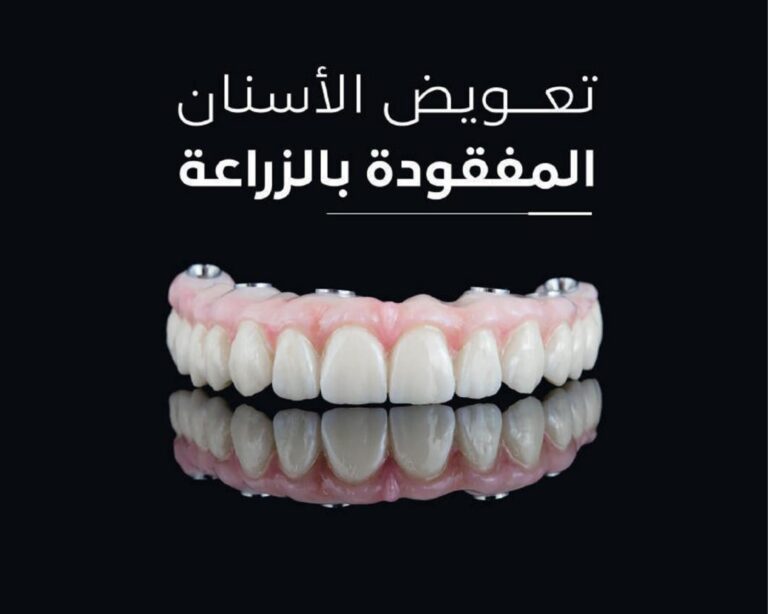

استشاري جراحة اللثة التجميليه وزراعة الأسنان

زراعة الأسنان بأحدث التقنيات الحديثة